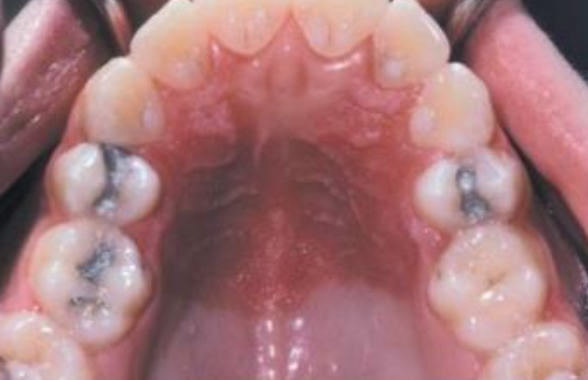

White Sponge Nevus

(Cannon disease)

體顯性 兩側的頰黏膜,出生時、孩童早期

• 口腔黏膜的正常角質化缺陷

• 對稱

• keratin 4 和 keratin 13 表現在上皮的棘狀上皮細胞層

• hyperparakeratosis, acanthosis

• spinous layer 清澈的細胞質

• 表層細胞核周圍嗜酸